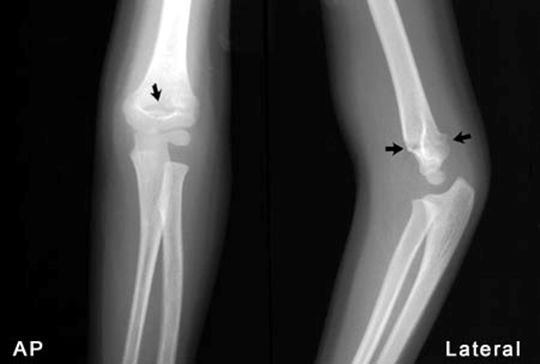

肱骨髁上骨折

肱骨髁间骨折